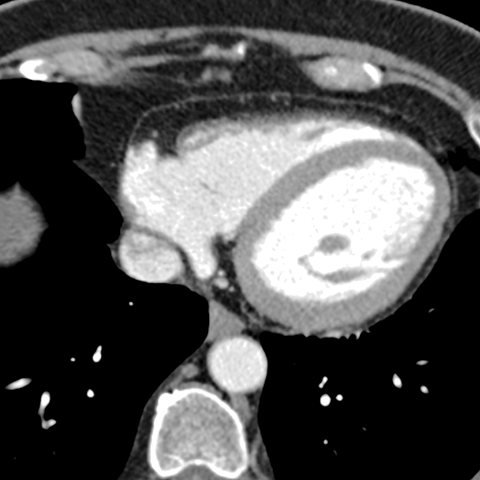

Normal Pericardium (Axial CT) [3 of 8]